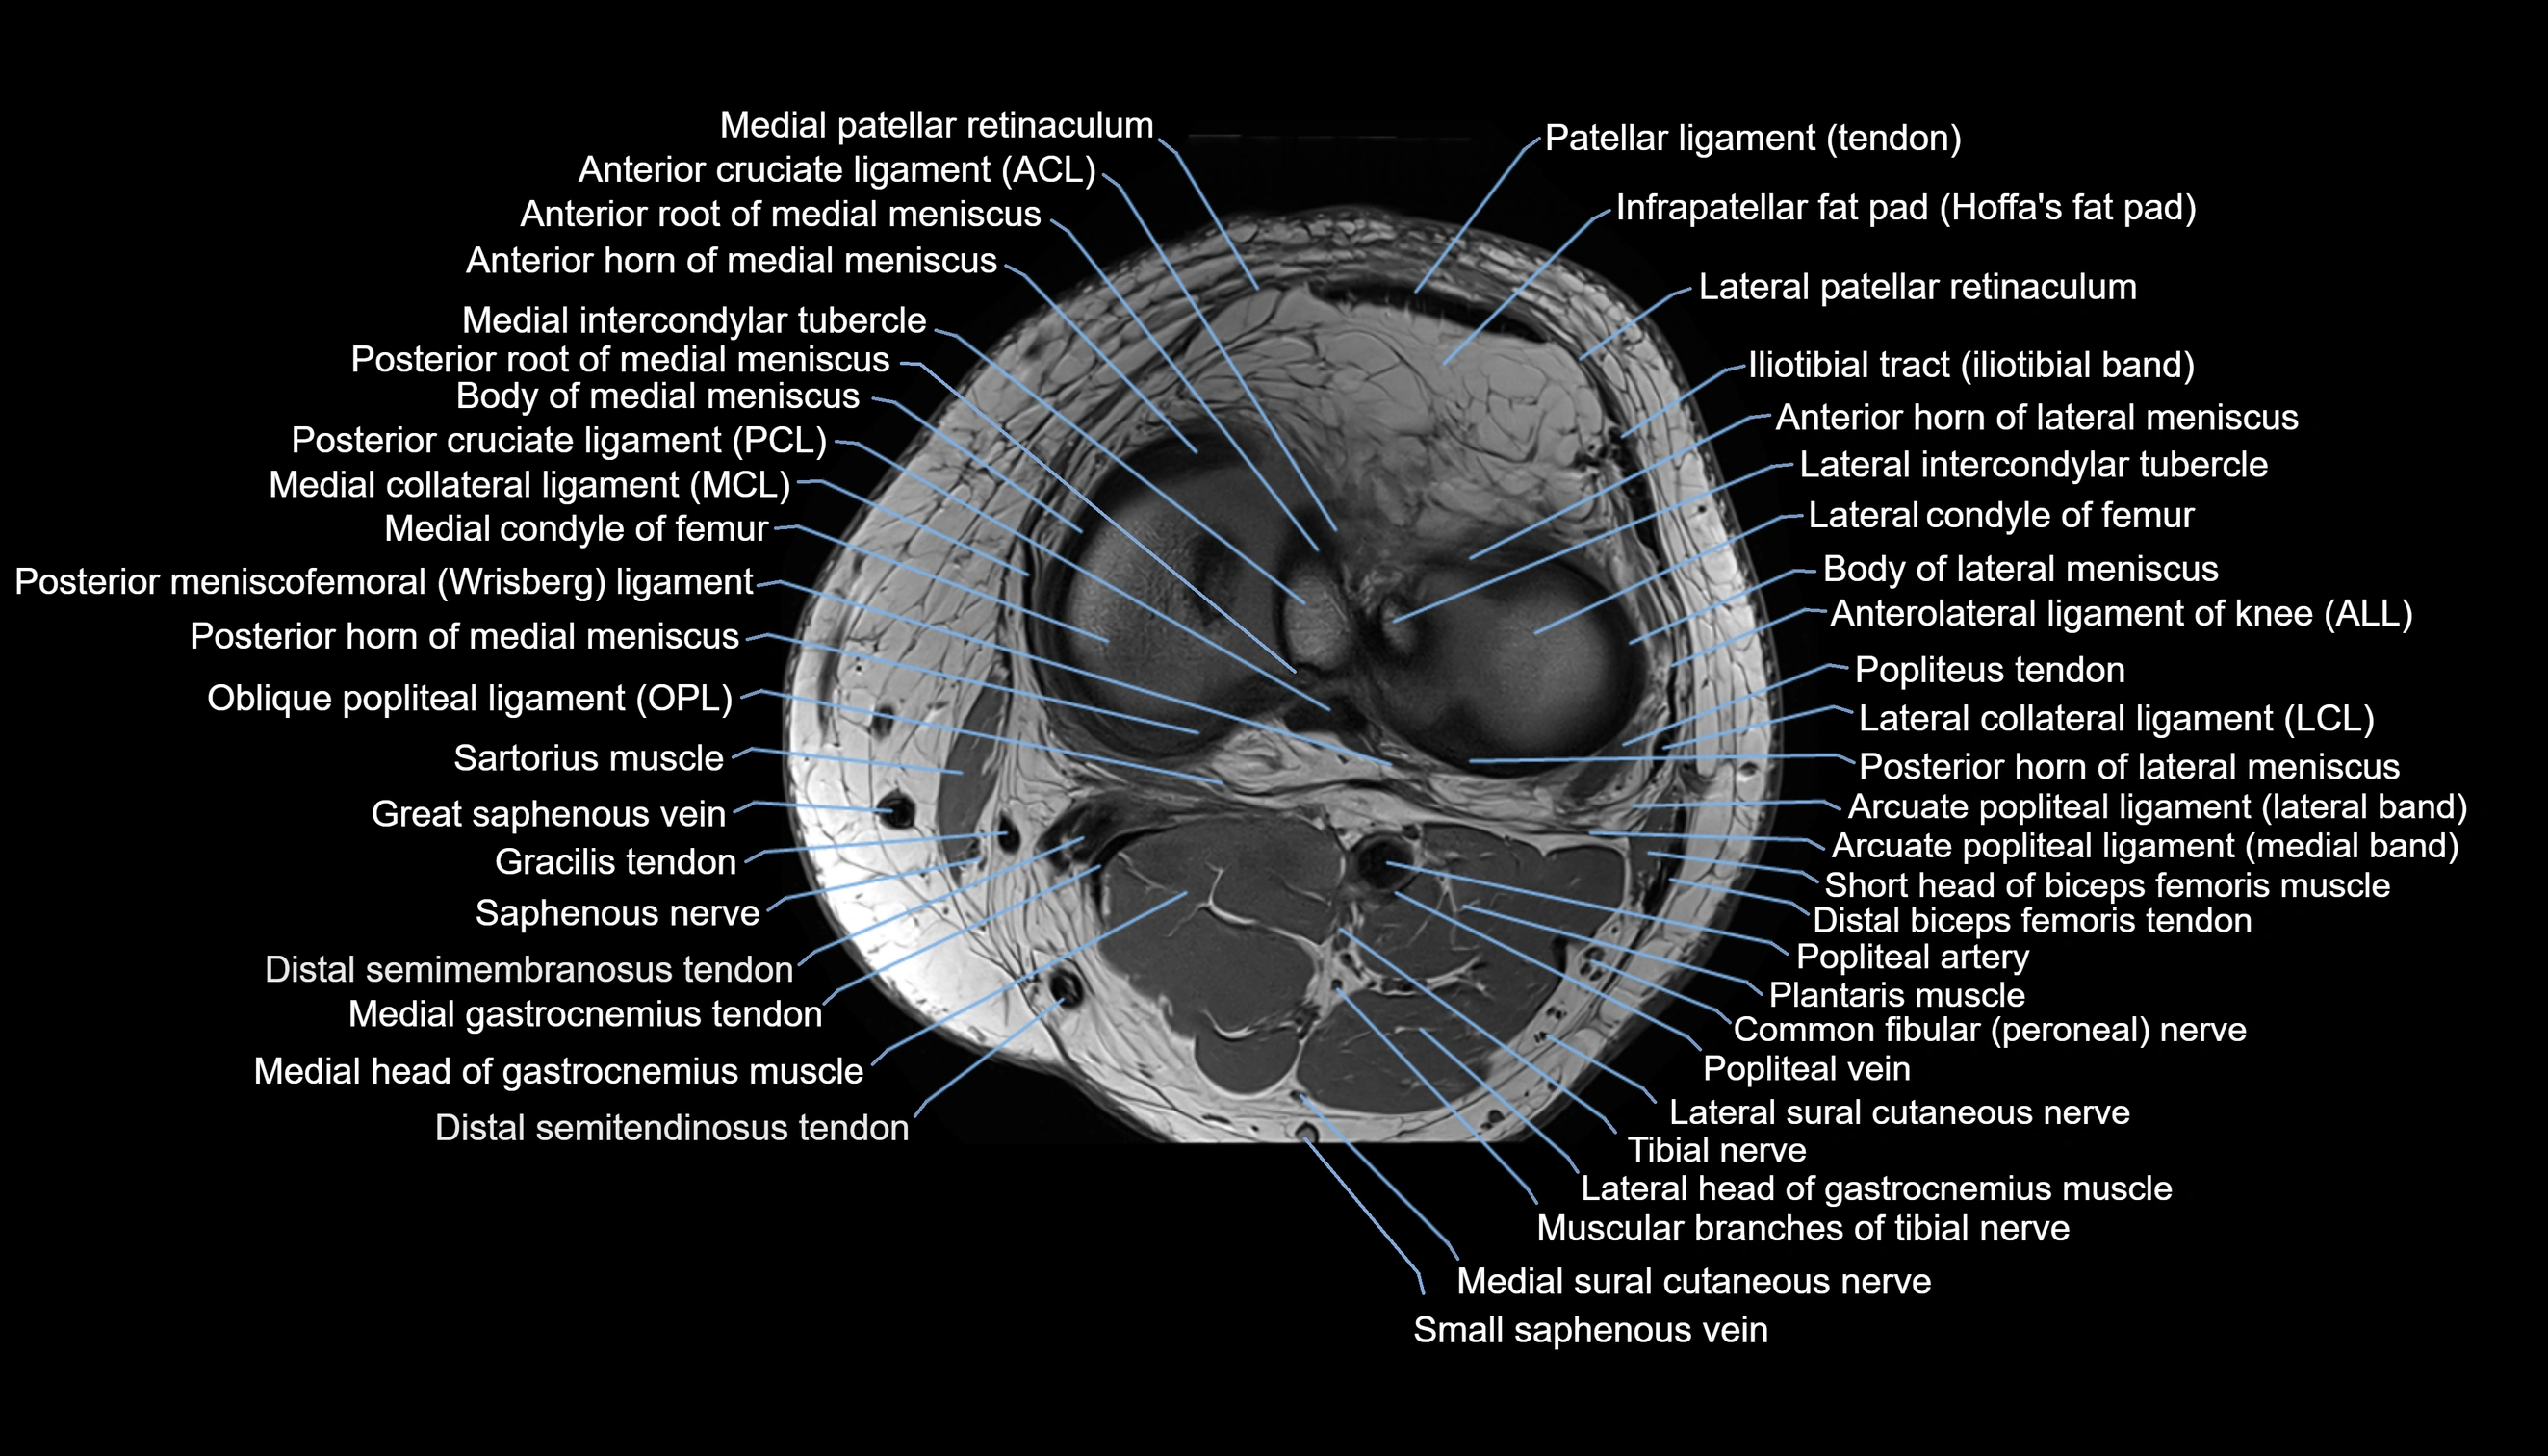

- Anterior cruciate ligament

- Anterior horn of lateral meniscus

- Anterior horn of medial meniscus

- Anterior root of medial meniscus

- Anterolateral ligament of knee

- Arcuate popliteal ligament

- Body of lateral meniscus

- Body of medial meniscus

- Lateral collateral ligament

- Lateral condyle of femur

- Lateral meniscus

- Lateral patellar retinaculum

- Medial collateral ligament

- Medial condyle of femur

- Medial meniscus

- Medial patellar retinaculum

- Oblique popliteal ligament

- Popliteal artery

- Popliteal vein

- Popliteus tendon

- Posterior cruciate ligament

- Posterior horn of lateral meniscus

- Posterior horn of medial meniscus

- Posterior meniscofemoral ligament